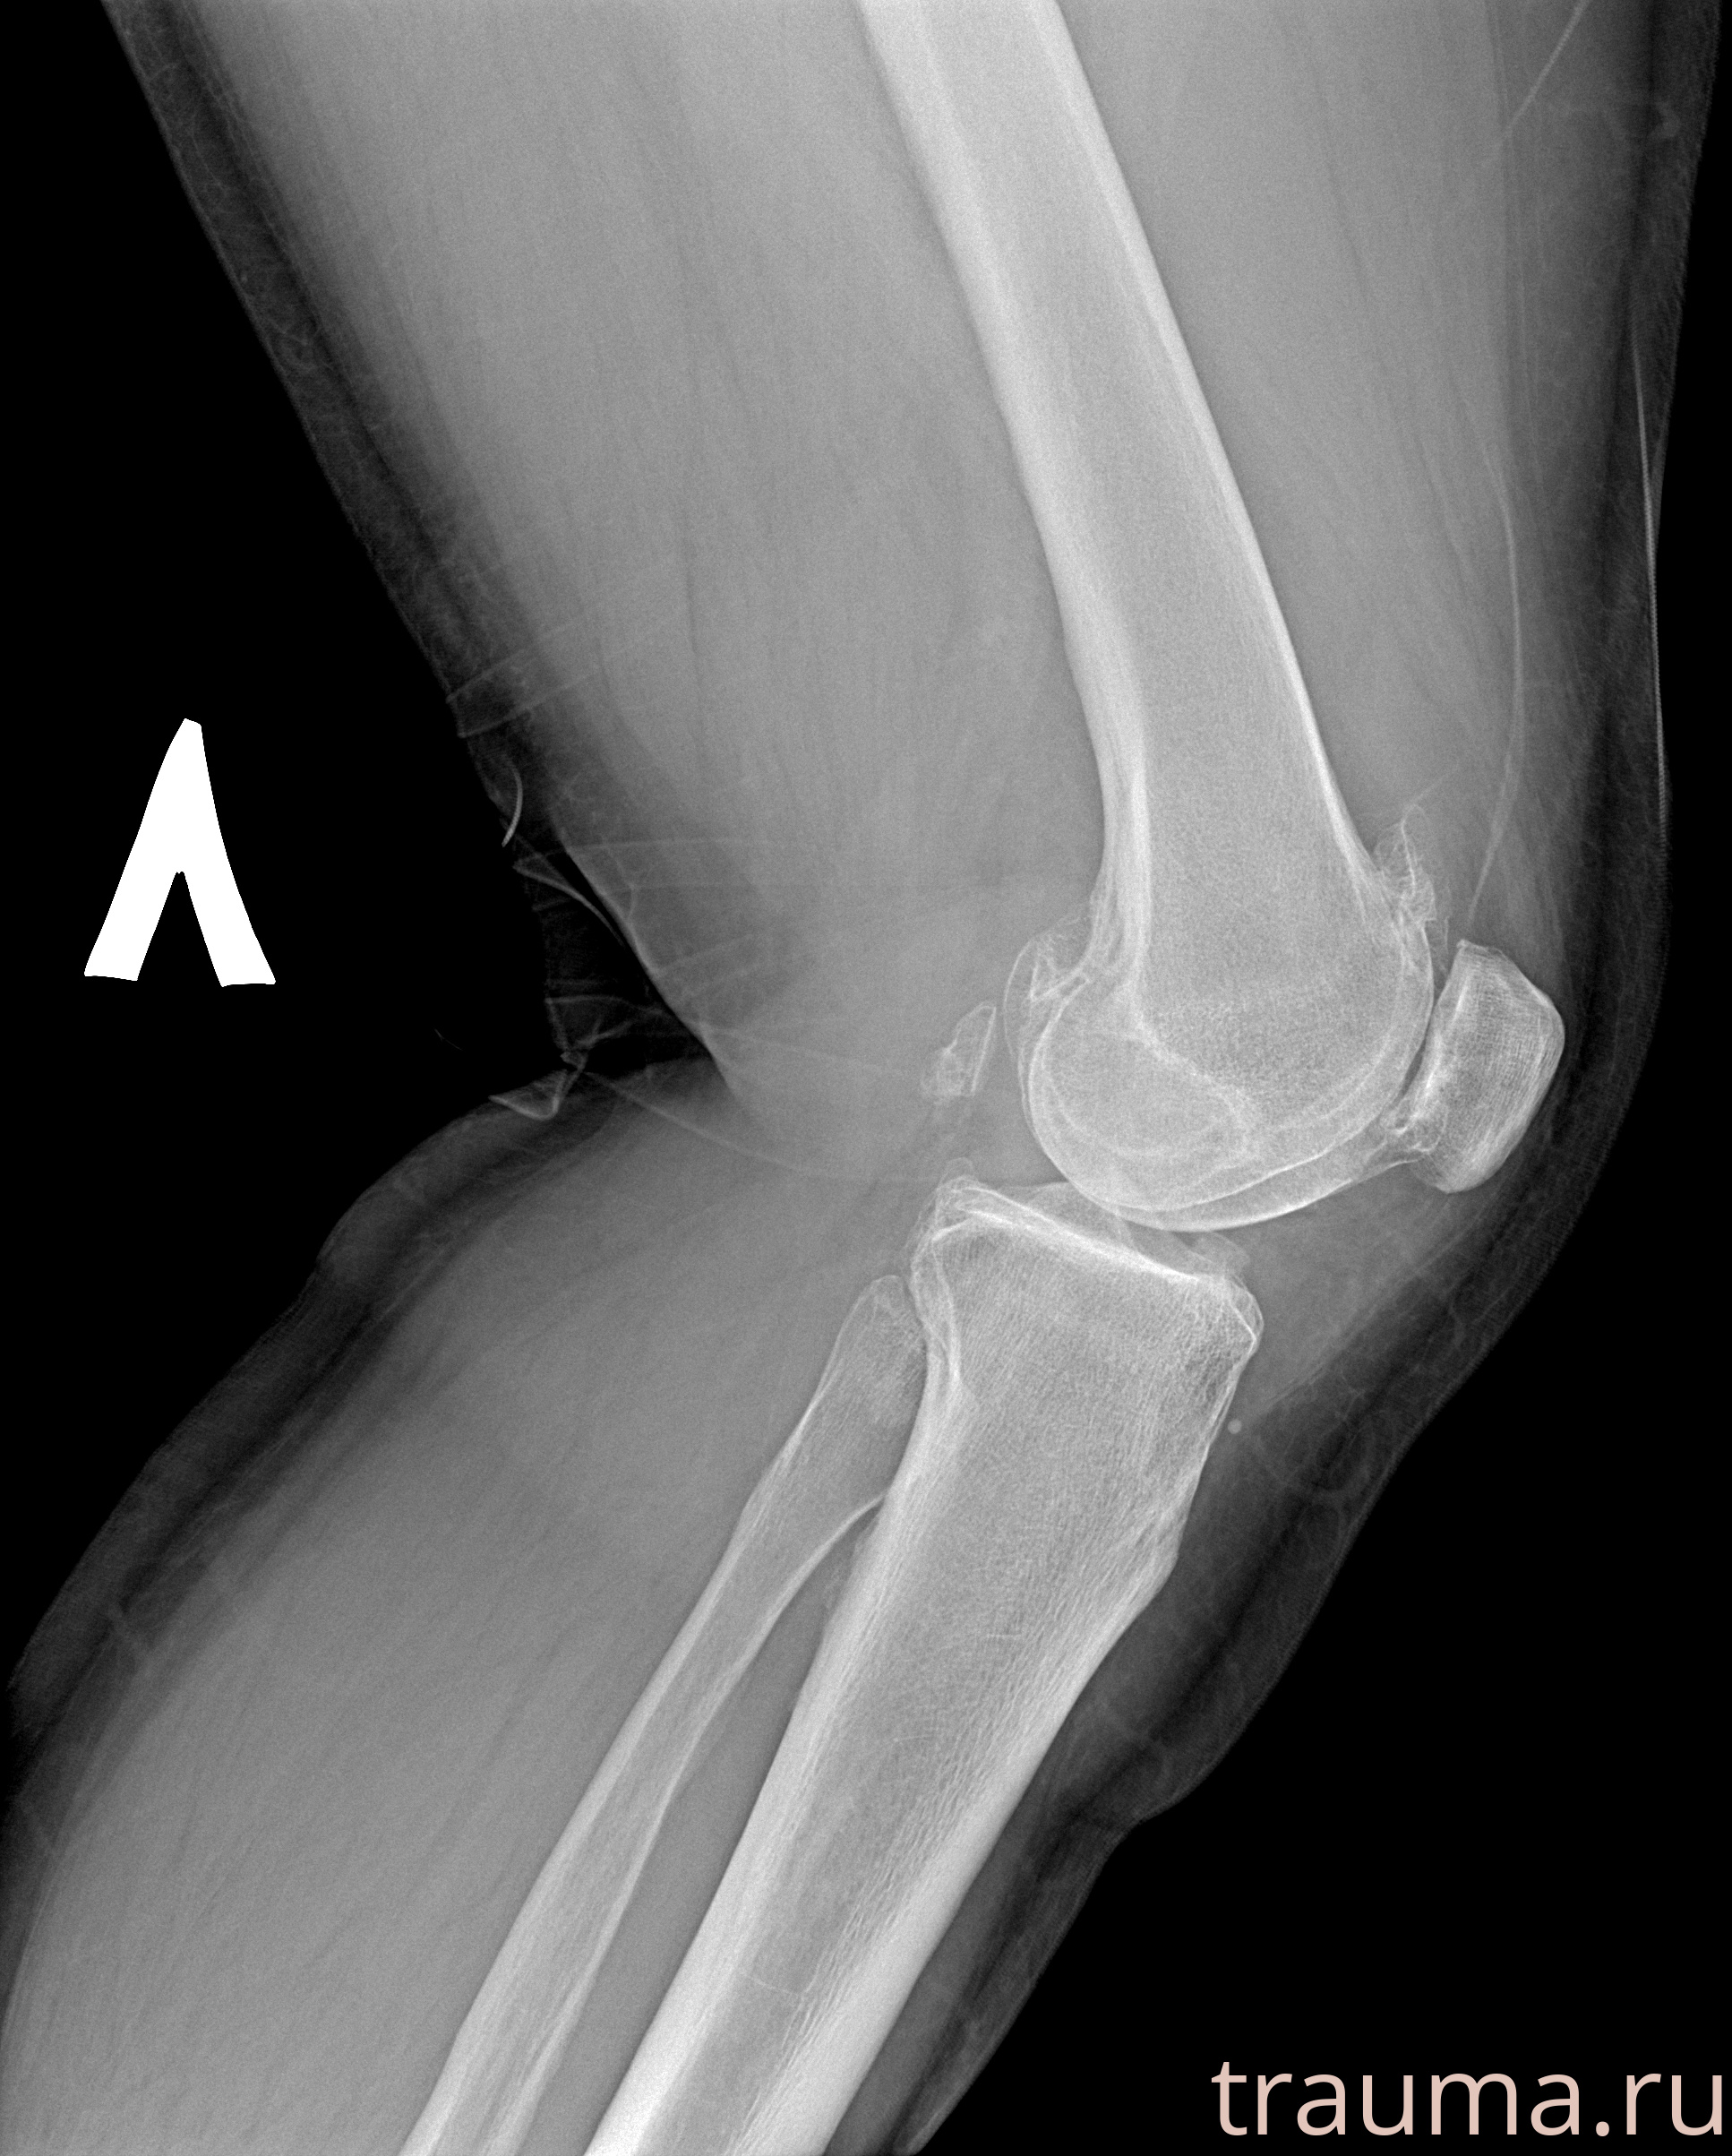

Рентген на дому: по вашему адресу приезжает врач-рентгенолог, травматолог-ортопед с мобильным рентгеновским аппаратом, проводит диагностику травмы или заболевания, делает необходимые рентгенограммы, дает рекомендации по дальнейшему лечению. Получить качественные снимки в домашних условиях возможно благодаря уникальной методике, разработанной МосРентген Центром для института  Склифосовского